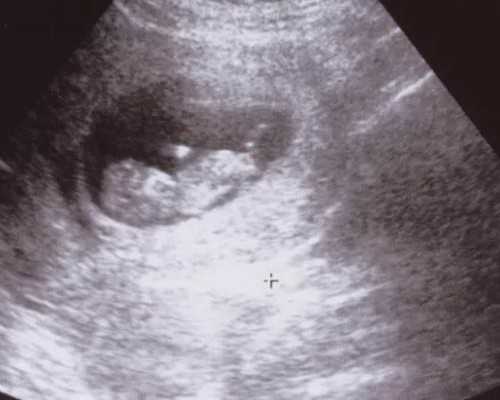

1. 首先,女性需要接受一些检查,以确定她是否适合供卵。这些检查通常包括血液检查、超声波检查、内分泌检查等。